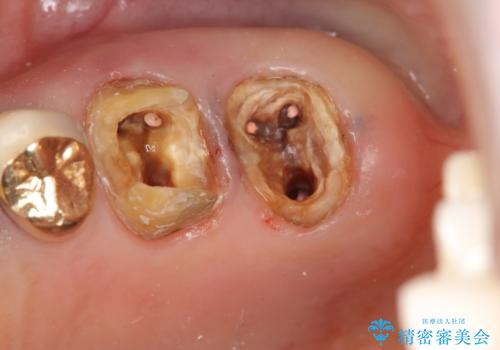

クラウンの除去・虫歯の除去、根管治療を行ったのち、上顎は強い咬合力に対し破折抵抗性のある咬合面をメタルにしたメタルボンドによる補綴を計画します。

今回は破れにくいセラミック治療としてメタルボンドを選択しました。

外側からは金属色の見えない設計となっています。